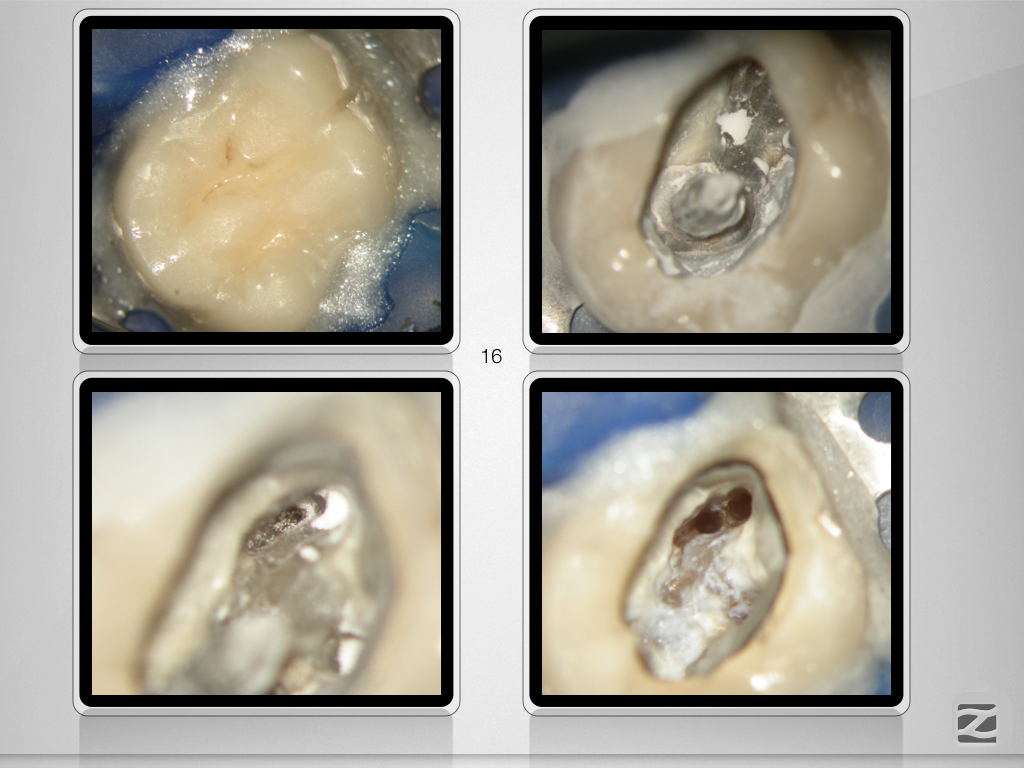

16-14D.007

Mein endodontischer Alltag